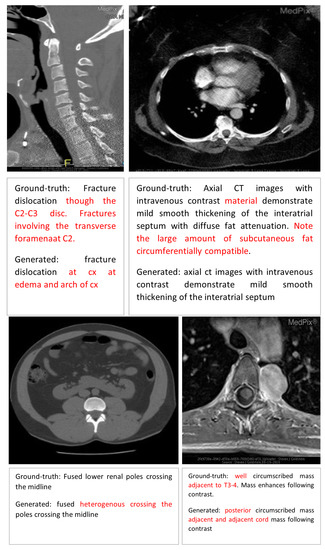

Error Analysis